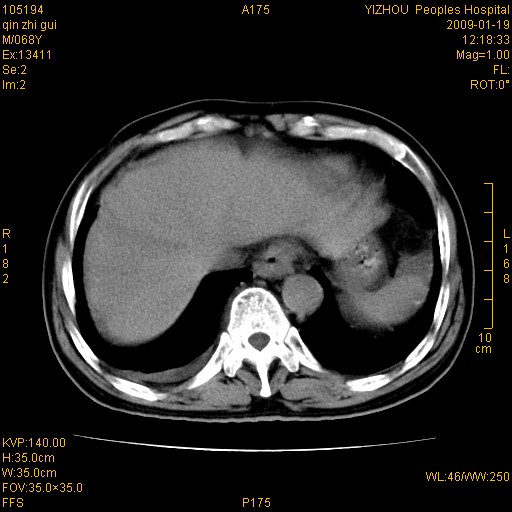

以下是引用随光逐影在2009-1-21 16:11:00的发言:[br]1)考虑肝右叶肝癌并肝静脉及门静脉瘤栓形成。2)肝硬化,少量腹水。3)胆囊炎。4)右侧少量胸腔积液。

病灶外缘凹凸不平,平扫低密度,增强动脉期有强化,门脉早显,静脉期及延期呈延迟强化,结合病史考虑右肝前叶巨块型肝癌可能性大,强化表现不除外胆管细胞癌